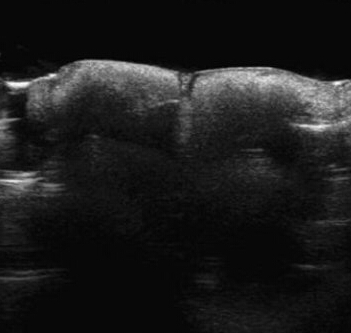

在研究的几项案例中表现为,胶原蛋白和透明质酸呈现出皮下形态规则的低回声团块,内部没有回声,胶原蛋白和透明质酸之间的超声图像没有明显的差别。鼻唇沟注射胶原蛋白(Evolencet)11周后,箭头提示许多形态规则的低回声团块,内部没有回声,在探头和皮肤之间使用了Aquaflex垫。鼻唇沟注射透明质酸(Restylanes)10周后,箭头提示皮下形态规则低回声团块,没有内部回声,在探头和皮肤之间使用了Aquaflex垫。